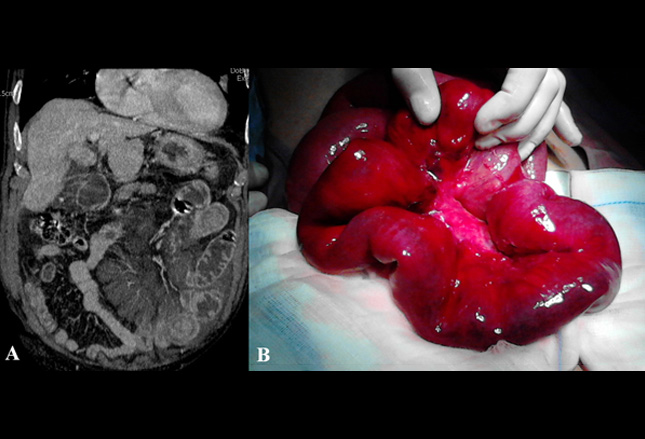

答案:C.气肿性胆囊炎

气肿性胆囊炎是由产气菌引起的胆囊壁感染。它可能是由继发于胆石症、免疫抑制或既往手术操作的血管损伤引起的。经典表现是老年糖尿病

患者右上象限疼痛和发烧。

X线片可显示胆囊壁内空气,可经CT成像确认(如图)。气肿性胆囊炎是外科急症,有15%-20%的死亡率。